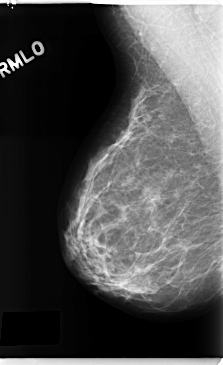

C_0271_1.RIGHT_MLO

RIGHT_MLO LINES 4736 PIXELS_PER_LINE 2888 BITS_PER_PIXEL 12 RESOLUTION 50 NON_OVERLAY